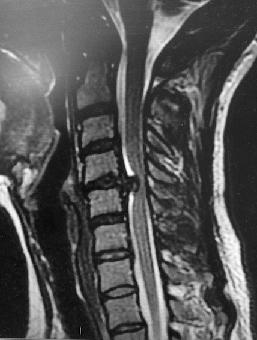

Hérnia de Disco

Em muitos casos, os sintomas relacionados a uma hérnia de disco começam durante o treinamento com pesos ou durante um movimento; em outros, o início é mais insidioso e é provavelmente o acúmulo de múltiplas lesões menores.,/p>

Atletas expostos a considerável carga axial, flexão e rotação, que ocorrem durante o levantamento de peso (e esportes que exigem trabalho pesado na competição ou treinamento) e esportes de impacto podem ter taxas mais elevadas de hérnia discal.

Os sintomas podem aparecer de forma sutil, com dor nas costas e espasmos, com pouco ou nenhum componente radicular (dor irradiada para o membro), embora a radiculopatia é freqüentemente presente.

Em muitos casos ocorre ruptura do disco (fissura do ânulo fibroso) sem necessariamente formar uma hérnia.

O exame físico da hérnia de disco, às vezes, pode revelar escoliose leve ou unilateral. A avaliação médica e estudos com imagens são muito importantes quando existe suspeita de hérnia de disco ou dor persistente.